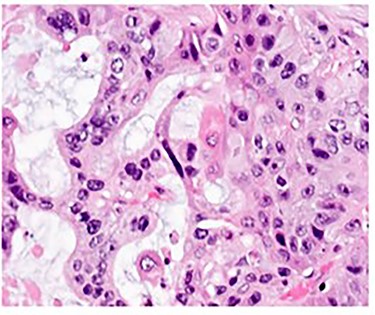

Pathologic analysis revealed an AJCC Stage IV (pT3, N0, M1) 7.7 cm moderately differentiated (histologic grade G2) adenosquamous carcinoma of the gallbladder with lymphovascular and perineural invasion, and tumor extension into adjacent liver, peritoneal surface and residual lesser omentum. Surgical margins were all negative. No tumor was identified in any of the eight portal lymph nodes obtained. Figure 6 shows a gross cross section of the gallbladder. Figure 7 shows H&E stain of the tumor demonstrating adenosquamous features. Figure 8 shows an H&E stain demonstrating peritoneal surface involvement. Figure 9 shows an H&E stain demonstrating involvement of the lesser omentum.